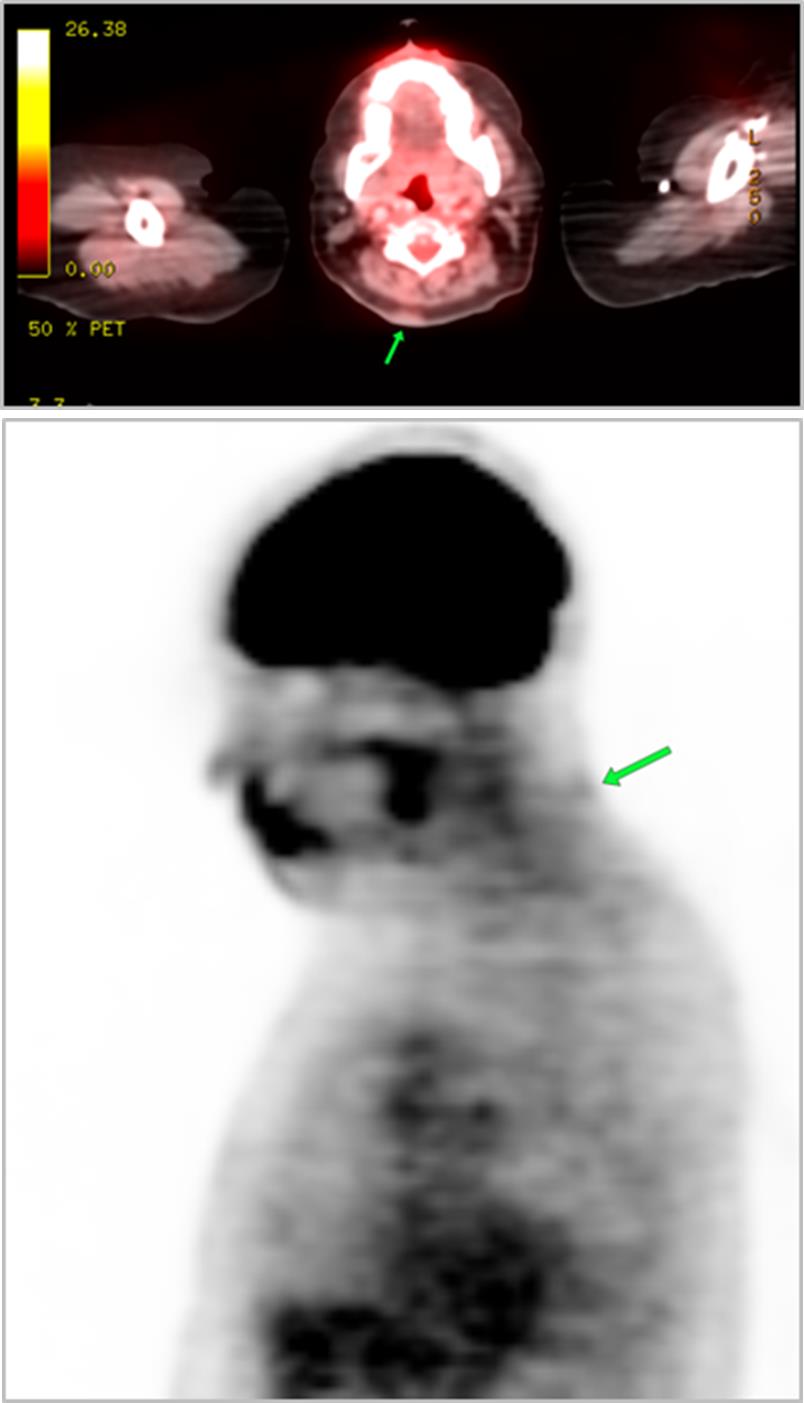

The most common cause of skin metastases in adult women is primary breast carcinoma, which comprises about 70% of cases [1]. Skin metastases have non-specific clinical appearances, making it challenging to differentiate them from other benign conditions [1]. We present a case of a 52-year-old female with type II diabetes and a three-month history of refractory skin lesions who did not respond to anti-inflammatory treatment. The patient subsequently complained of a right breast lump, evaluation of which led to the diagnosis of bilateral synchronous invasive lobular carcinoma.